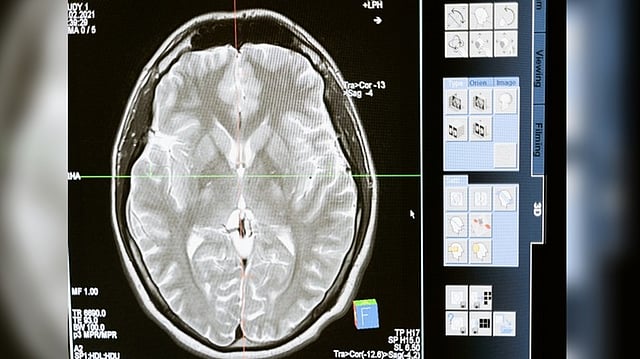

Fungal intruder shrinks, develops to aid infection spread: Study

WASHINGTON: According to new research from the University of Utah Health, a fungus that is a major cause of fungal meningitis undergoes a remarkable change once it enters the body, allowing it to infect the brain.

In mouse studies, the fungal intruder shrinks and develops features that aid infection spread in a matter of days as it moves through the body. The findings of the study were published in the journal Cell Host & Microbe.

The discovery could lead to new strategies for blocking Cryptococcus neoformans infection and preventing detrimental effects on the host. C. neoformans is the leading cause of a rare but deadly swelling of the brain that occurs in people with weakened immune systems.